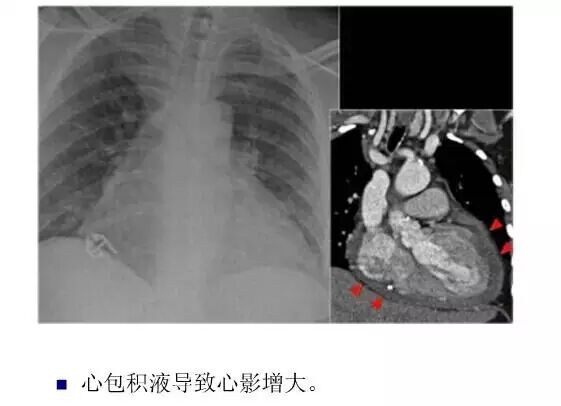

平片如何看心衰